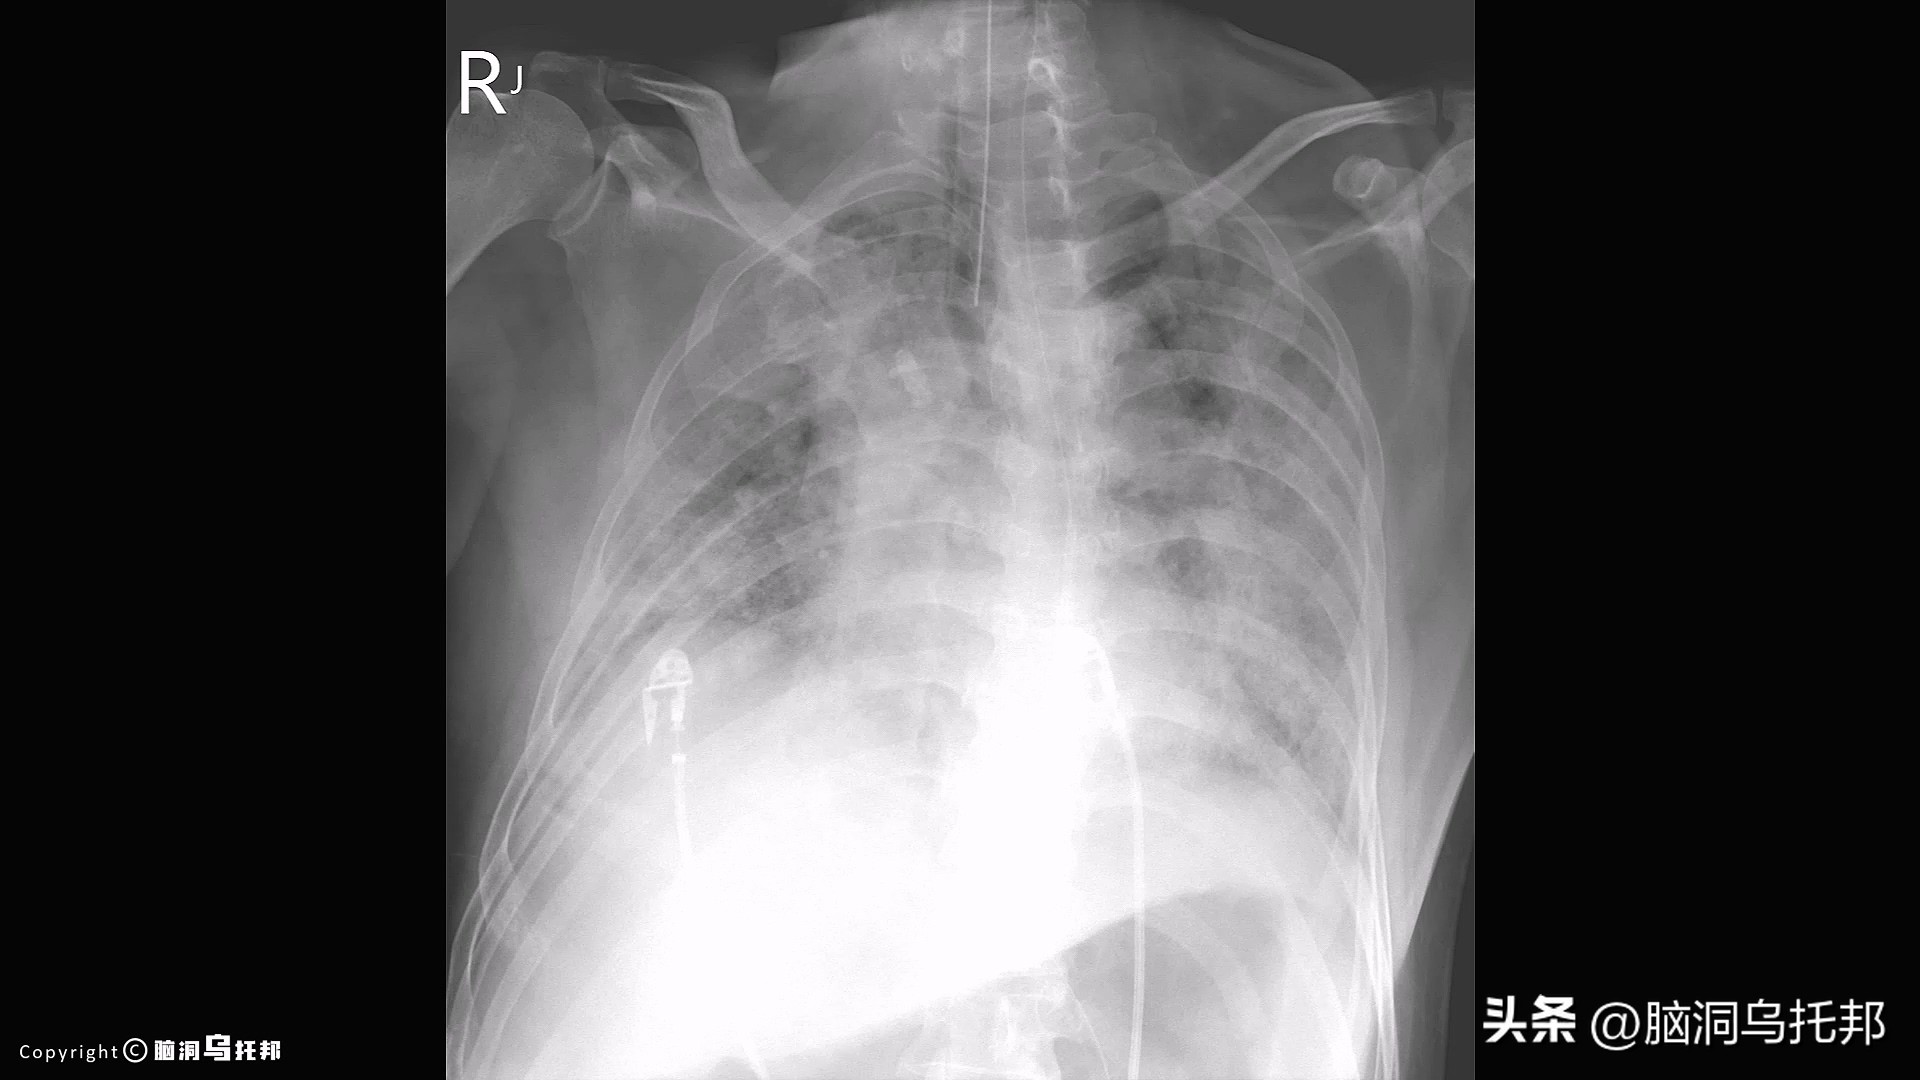

被新冠病毒感染的肺部开始聚集大量的组织碎片和液体,

因为免疫细胞的运输靠的是体液和血液。

结果就是肺部逐渐被液体浸没,呼吸困难,血氧下降,

这就是我们在肺部CT上看到的大白肺。